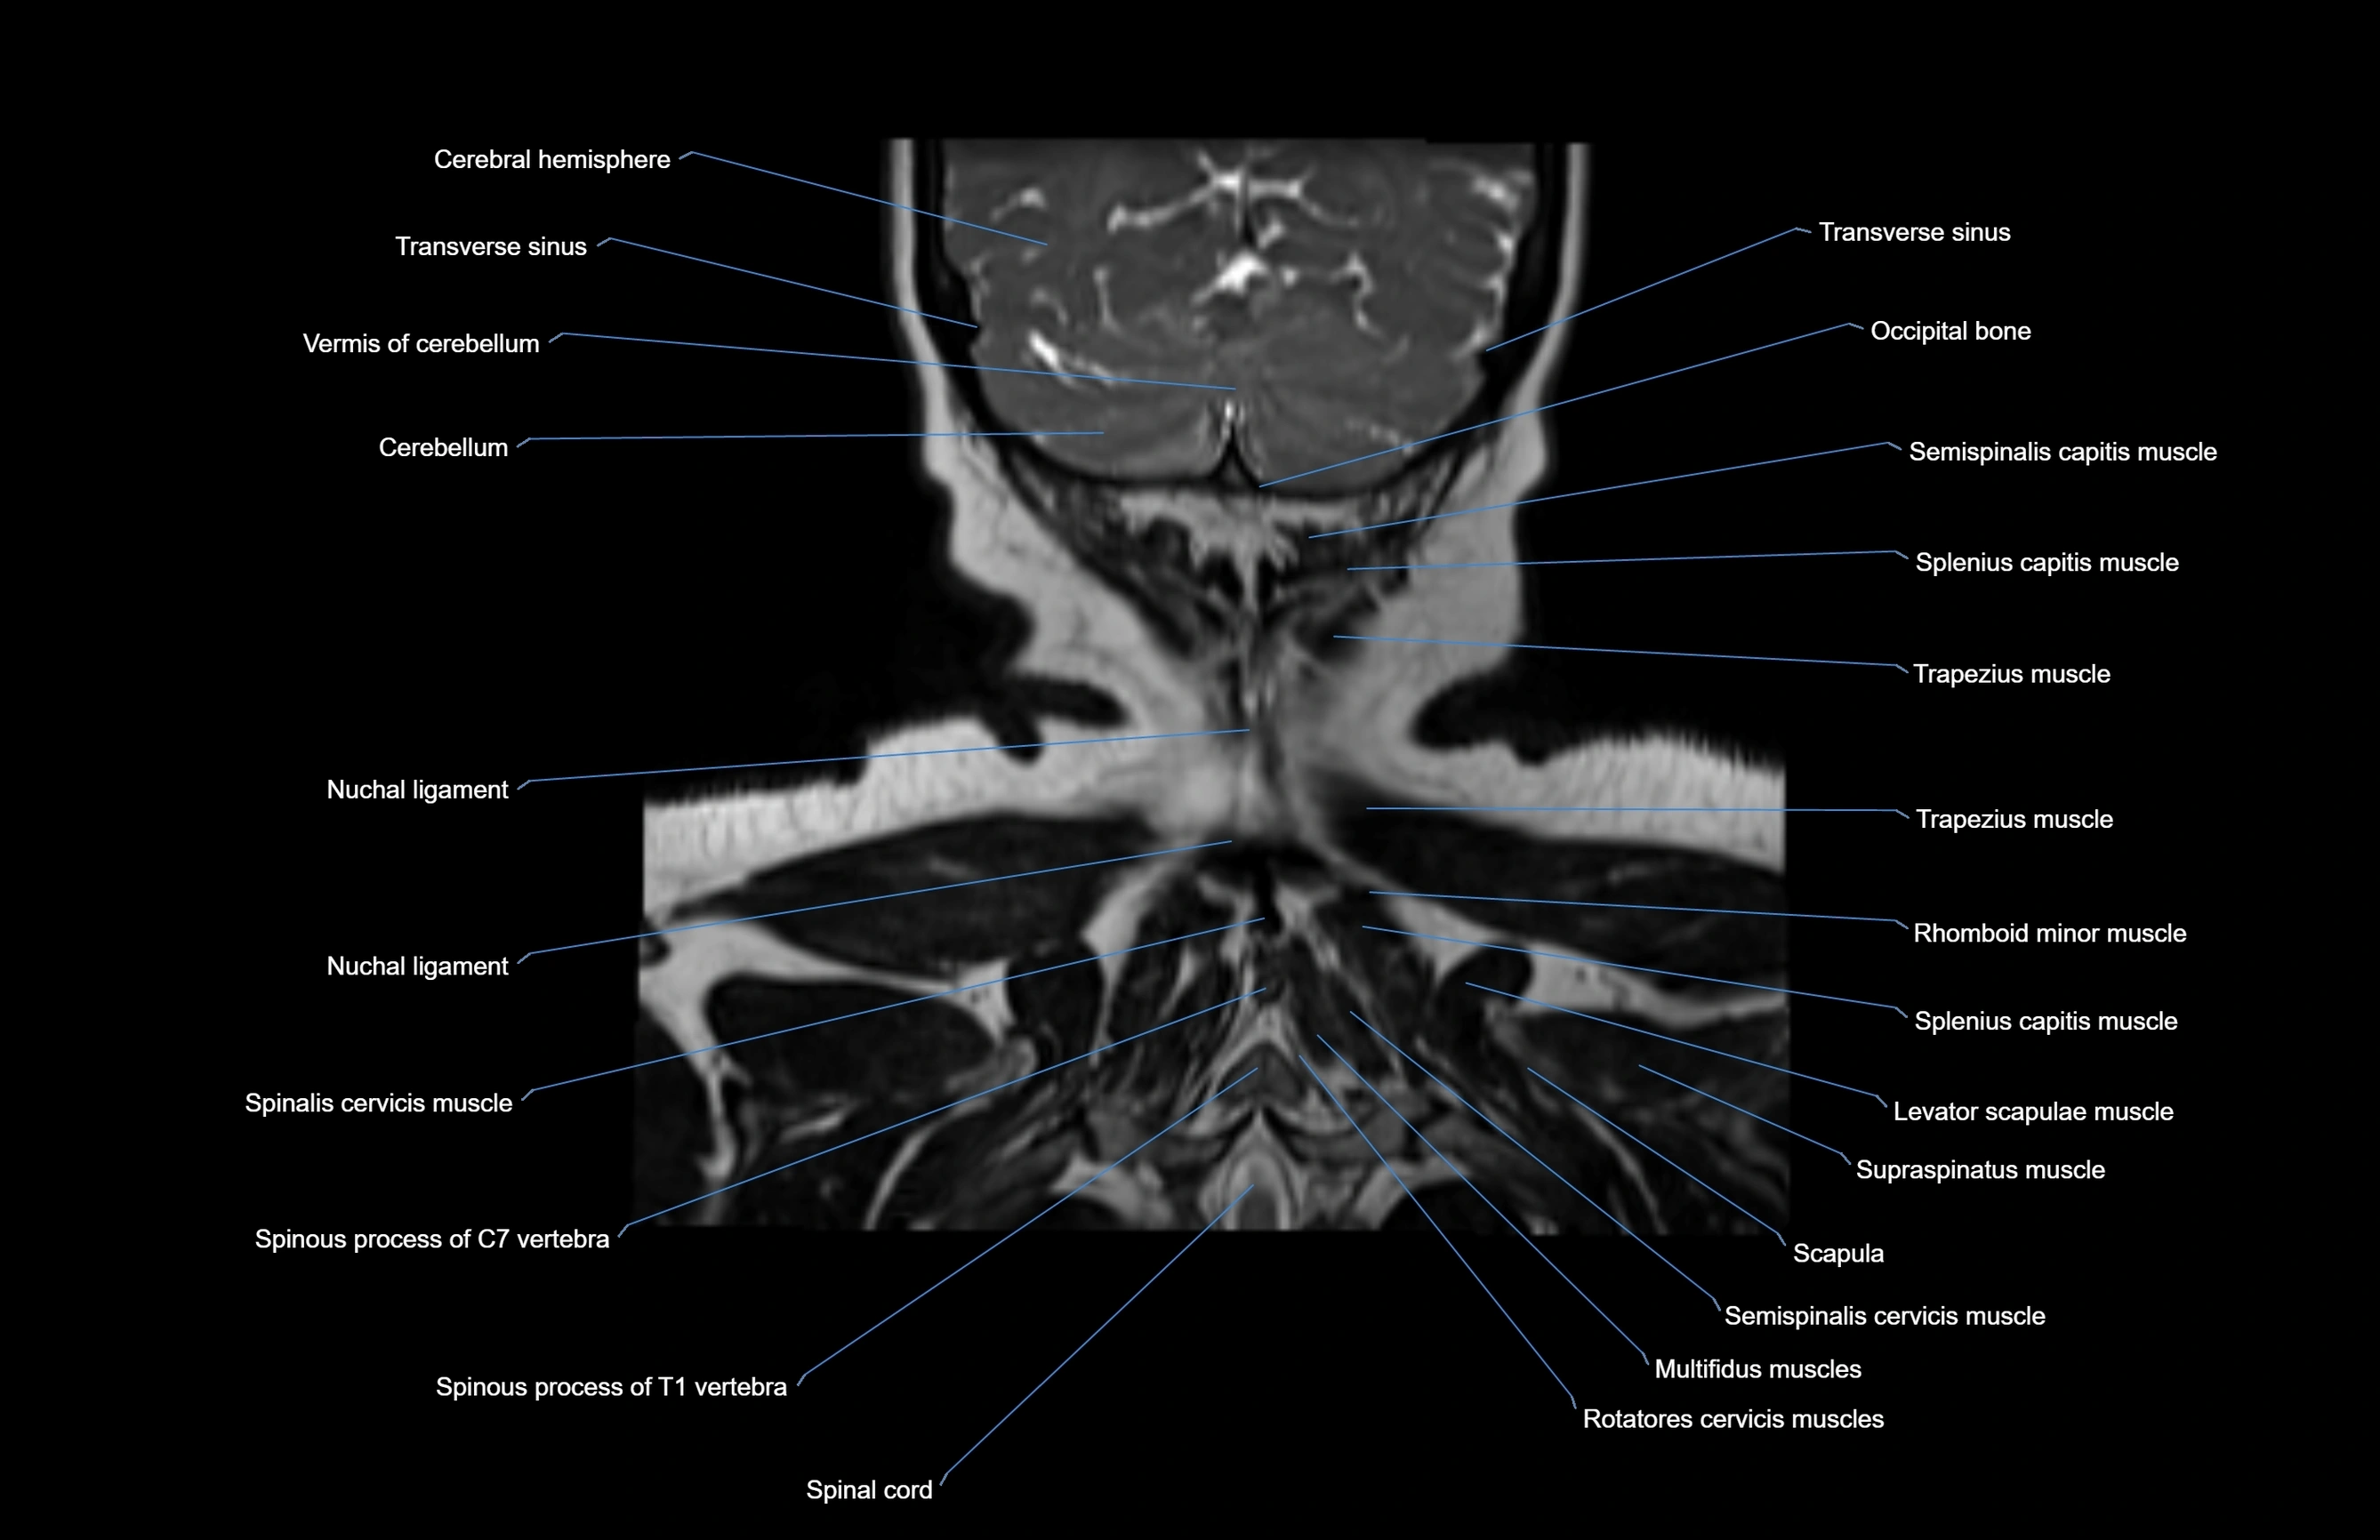

- Cerebellum

- Nuchal ligament

- Rotatores cervicis muscle

- Rotatores cervicis muscles

- Semispinalis capitis muscle

- Semispinalis cervicis muscle

- Spinal cord

- Spinalis cervicis muscle

- Spinous process of vertebra

- Splenius capitis muscle

- Trapezius muscle